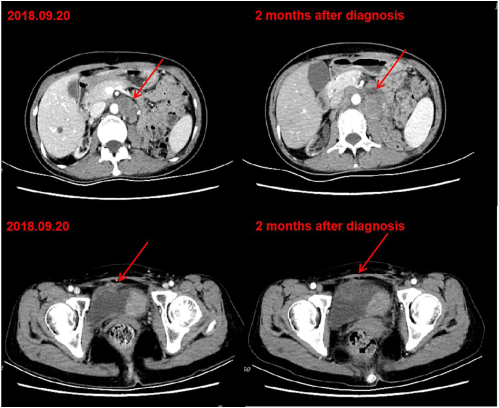

2018年9月,患者膀胱局部复发,盆腔淋巴结和腹膜后淋巴结出现转移。考虑到顺铂的肾毒性和双重化疗的候选性差(ECOG评分2分),患者在第1天和第8天接受1000mg/m2的吉西他滨化疗,每3周一次。经过两个周期的吉西他滨治疗,患者的病情继续进展(图1)。

图1. 化疗后CT显示肿瘤进展